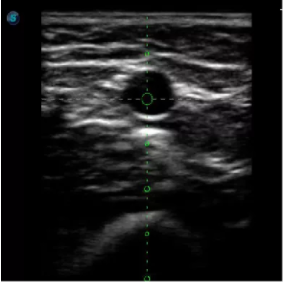

取卵臨床圖

傳統(tǒng)腔內(nèi)探頭采用直柄設(shè)計,在搭配穿刺架使用時,手術(shù)空間小,不易操作;生殖專用的曲柄探頭,探頭柄采用彎曲成角度設(shè)計,可實現(xiàn)監(jiān)視、取卵兩不誤,搭載穿刺架時,可以清晰顯示穿刺針的進針過程、深度和位置,實時監(jiān)視取卵全過程,保障取卵操作精準(zhǔn)與安全。